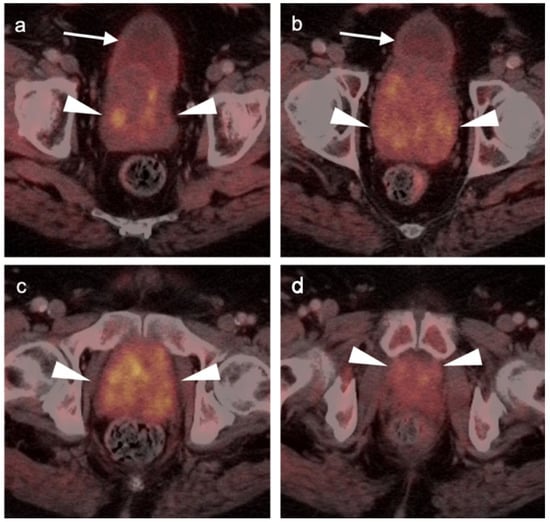

3.1. Prostate Cancer